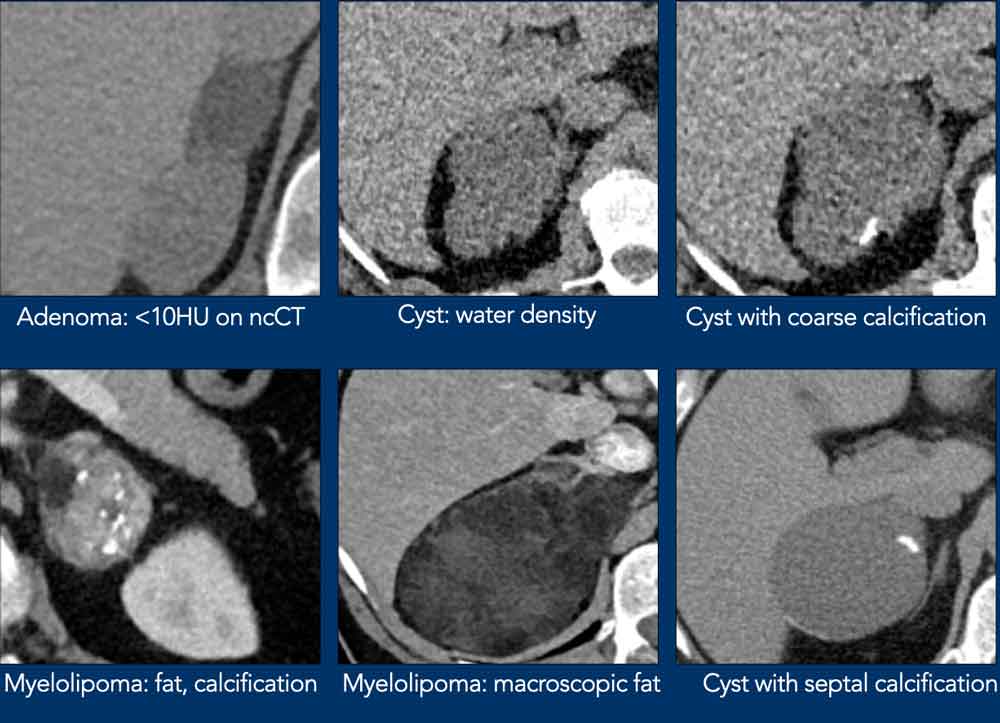

Here some examples of typically benign lesions.

Lipid-rich adenoma

70% of adenomas contain high intracellular fat and will be of low attenuation on unenhanced CT [4,5].

A density equal to or below 10 HU is considered diagnostic of a lipid-rich adenomas.

Using a safe threshold value of 10HU on a native CT scan results in a sensitivity of 70-79% and a high specificity of 96-98% for the diagnosis of an adenoma [5-7].

Cyst

An uncomplicated cyst is a well-defined lesion of water density that does not enhance.

A cyst has a thin wall and may have thin septa.

It may be an endothelial cyst or a pseudocyst, which are the most common, or a true epithelial or parasitic cyst (both rare) [5].

Pseudocysts may have thicker walls.

Hemorrhage or debris may cause increased internal attenuation.

Both benign and malignant tumors may show cystic degeneration and necrosis.

In those cases density measurements are unreliable.

Features of an underlying tumor may be an irregular thick wall of 5 mm or more and mural, septal or solid enhancement [5].

Lesions with benign calcifications Lesions with benign calcifications

Lesions with benign calcifications

Coarse rounded, peripheral or septal calcifications are typically benign and may be seen in:

• Adenoma

• Myelolipoma

• Trauma

• Granulomatous infection

Bilateral calcifications also suggest a benign origin.

Punctate, dystrophic and irregular calcifiations are not typically benign and can be seen in:

• Adrenocortical cancer

• Adrenal metastases

Myelolipoma

Myelolipomas are benign tumors composed of bone marrow elements.

Usually they are easy to recognize on CT or MR because they contain areas of macroscopic fat.

Calcifications are seen in 24% of cases.

The adrenal mass seen here on CT contains macroscopic fat, which is specific for the diagnosis myelolipoma.